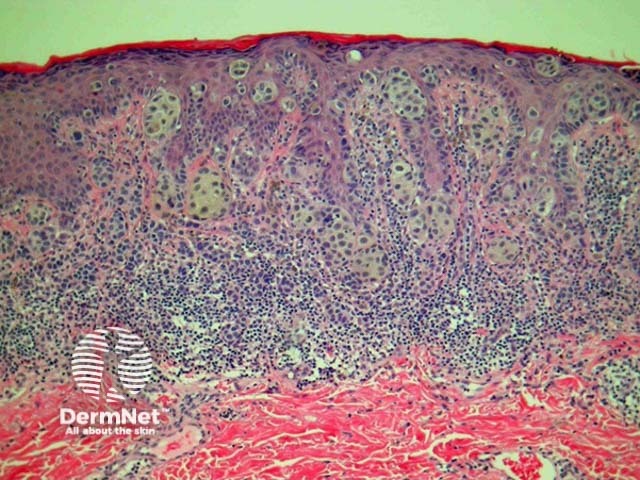

Most melanomas have an initial radial growth phase within the epidermis and sometimes within the papillary dermis (figure 1, 2), which may be followed by a vertical growth phase with deeper extension (figures 3, 4). The exception to this is nodular melanomas, which either skip the radial growth phase or the radial phase is rapidly overrun by the vertically growing tumour. It is also possible that they arise within dermal melanocytes. It has been proposed that lesions in the radial growth phase are incapable of metastasis, however there are numerous examples of thin melanomas that have behaved aggressively, even without convincing evidence of vertical growth.

Figure 1

Figure 2

Figure 3

Figure 4

Superficial spreading melanoma (SSM) is the most common melanoma variant. These tumours are most commonly found on the back in males and legs in females. Histologically they are characterised by atypical epithelioid melanocytes, found singly or in clusters, scattered throughout the epidermis (known as ‘buckshot scatter’). Tumour cells have abundant cytoplasm, nuclear pleomorphism and prominent nucleoli. Melanocyte proliferation can be seen extending over the tips of the papillae in continuity from one rete ridge to another. Adnexae may be involved. Thinning or consumption of the epidermis may occur. Invasive dermal components show lack of maturation and varying degrees of atypia. See Figures 10, 11, 12, 13, 14, 15.